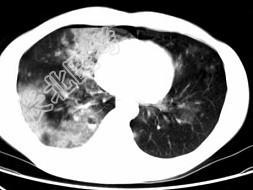

- 单项选择题男,28岁, 外伤后1小时行胸部CT如图,其最可能的诊断为 ( )

E、双肺挫伤